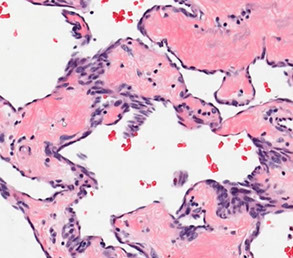

Epithelioid Hemangioendothelioma (EHE)

A, Epithelioid hemangioendoethelioma is composed of epithelioid cells with abundant eosinophilic cytoplasm that often contains vacuoles. B, The endothelial nature of the cells is confirmed by erythroblast transformation-specific transcription factor (ERG) staining.

Epithelioid / histiocytic hemangioendothelioma

Intermediate grade vascular malig in extremities of older adults derived from a vein (in 50%) ; arise from a small to medium-sized vessel

- most aggressive form of hemangioendothelioma (significant morbidity and mortality)

- MC in lung and liver, with a minority in ST, bone

-- sometimes more indolent when occurs in skin / ST

- can be multicentric, but no real specific clinical appearance

Gross: up to 18 cm

Micro: cords / small nests of round endothelial cells c lots of reddish cytoplasm that expand the vessels as they extend centrifugally from the lumen to the soft tissue in myxoid / mucinous sclerotic background

- blister cells c red cell fragments, which are tumor cells trying to form vascular lumens (similar to what may be seen in lobular breast ca)

-- can have vacuoles in lots of vascular tumors (blister cells are NOT specific for EHE) with plump endothelial cells

- usually does not make well-formed infiltrating vascular channels (like angiosarcoma does); good to distinguish from angiosarc

- lumen filled c necrotic debris, tumor and dense collagen

- round and possibly indented nuclei c intracytoplasmic vacuoles

- minimal mits, atypia or necrosis; though can be significant in small subset

IHC: (+) ERG, FLI1, CD34, CD31; many are keratin positive (CK+)

Genes: t(1;3)(p36;q25) WWTR1-CAMTA1 fusion (in nearly all cases)

- small subset have YAP-TFE3

- can test for FISH in difficult cases